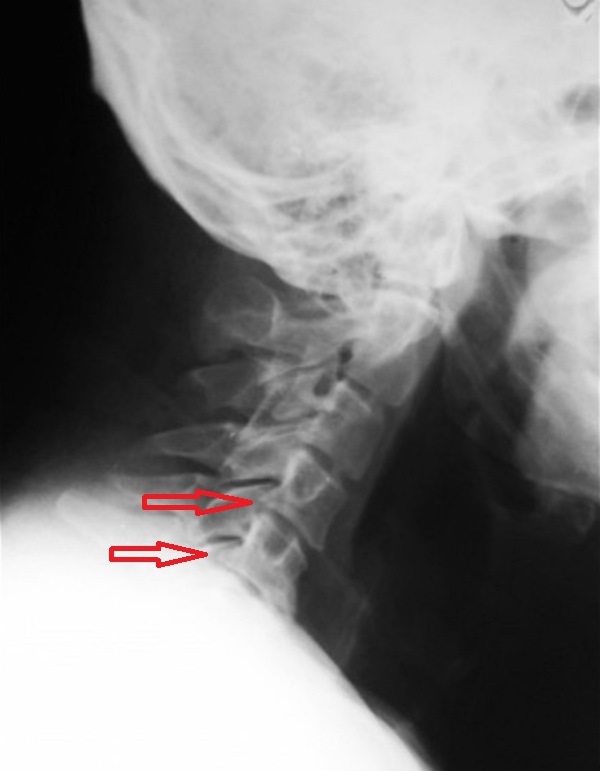

Спондилез

Так называется хроническая дегенеративно-дистрофическая патология, причиной развития которой становятся травмы, перегрузки, естественное старение организма. Заболевание сопровождают деструктивные изменения межпозвонковых дисков, а точнее их передних отделов. Обызвествляется передняя продольная связка, образуются множественные остеофиты. Неврологи выделяют следующие ведущие признаки спондилеза:

- непостоянные боли;

- ограничение подвижности;

- быстрая утомляемость при нагрузках.

Не только возникшие изменения ограничивают движения в шейном отделе, но и сам человек. Таким способом он снижает вероятность появления болезненных ощущений.

Диагностика

Для выявления деформации костных структур при остеохондрозе, полиостеоартрозе, спондилезе наиболее информативна рентгенография. Деструктивно-дегенеративные изменения хрящевых тканей, в том числе межпозвоночных грыж, а также связочно-сухожильного аппарата обнаруживают с помощью УЗИ, МРТ, КТ.